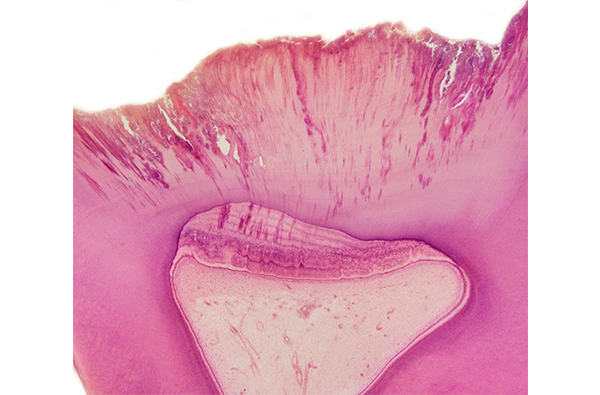

- 口腔組織学:歯科医師にとって特に重要になる、歯や歯周組織を含めた口腔・顎顔面領域の構造物について、顕微鏡レベルでの構造について学びます。

- 歯の病変:歯に生じる様々な病気(形成異常、う蝕、歯髄炎など)の原因や、その病気により正常構造がどのように変化するのか、などを学びます。

- 口腔・顎顔面領域の構造物の発生、成長、再生に関する研究